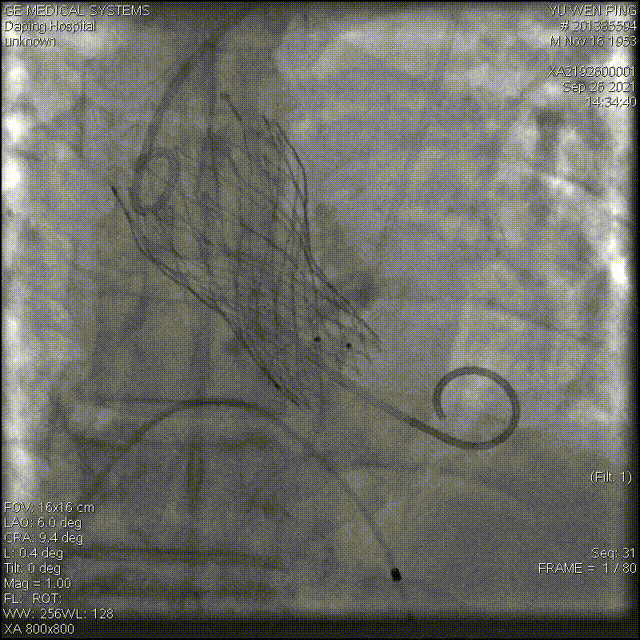

术中影像

以 Seldinger法穿刺右桡动脉,使用Pig造影导管行主动脉根部造影

20mm球囊预扩,有腰无漏

造影确定释放位置

释放成功,但存在中度瓣周漏,经20mm球囊后扩,造影见微量瓣周漏,较前明显好转